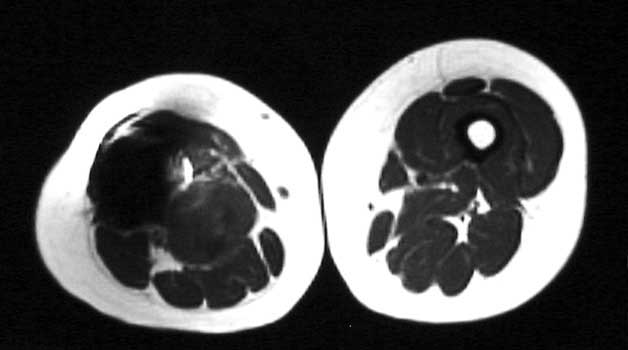

Mass in patient with modular endoprosthesis placed after resection of femur for osteosarcoma. Axial (fig A) and coronal reformatted images (fig B) clearly demonstrate mass adjacent to modular endoprosthesis. 14 gauge core needle biopsy performed under CT guidance (fig C) demonstrated recurrent osteosarcoma

Recurrent osteosarcoma in patient status post resection of femur and placement of modular endoprosthesis. Axial T1 and STIR sequences clearly demonstrate mass adjacent to endoprosthesis.